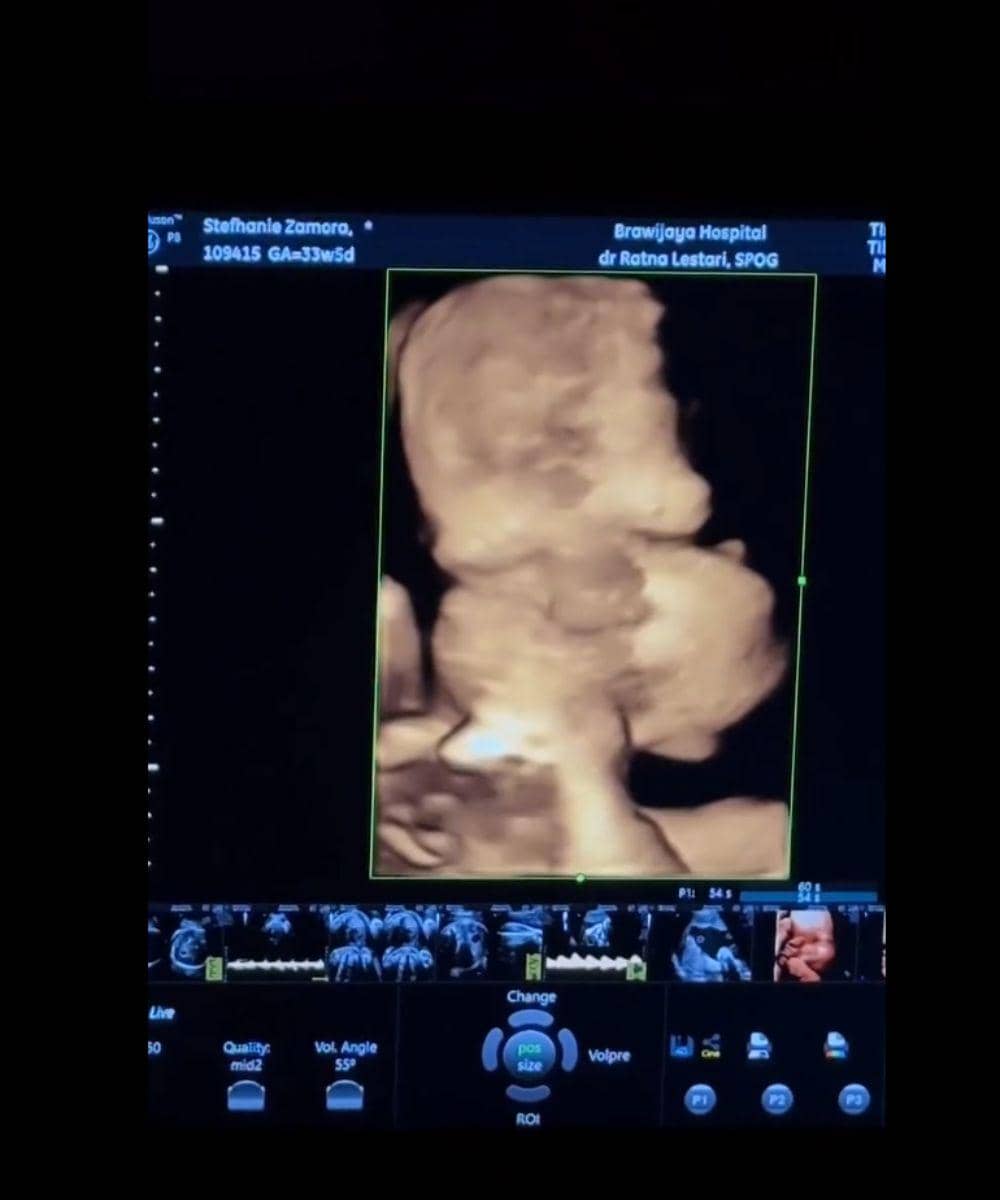

4. Potret calon anak pertama Steffi melalui hasil USG

Saat melakukan pemeriksaan USG, proses tersebut memperlihatkan visual janin dengan sangat jelas. Kehamilan Steffi yang memasuki trimester akhir membuat bentuk wajah bayi terlihat semakin sempurna, mulai dari hidung, pipi, hingga struktur wajah kecilnya yang menggemaskan.

Hal yang semakin menggemaskan adalah sang bayi tampak sedang mengisap jempol saat pemeriksaan berlangsung. Gerakan tersebut terlihat jelas di layar monitor. Selain itu, netizen juga banyak yang menyadari bahwa hidung sang putri sudah terlihat mancung.